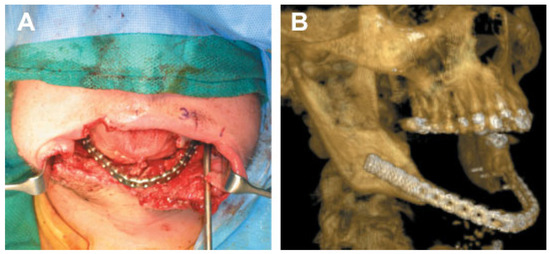

Nine months after injury, Patient 4 complained of drooling and difficulty eating. CT images revealed malunion of the anterior mandible fracture and bilateral bony ankylosis of craniomandibular articulations (Figure 13A,B). The patient also had lower lid ectropions, lower lip eversion, microstomia, chin ptosis, and lip incompetence secondary to burn scar contracture and malunion of the anterior mandible (Figure 13C–E).

Figure 13.

Nine months after injury. (A,B) Mandibular ankylosis and malunion are apparent. (C–E) Severe contractures, hypertrophic scars, ectropion, lip retraction, microstomia, and limited range of motion are directly related to burns and mandibular fractures. (Images are courtesy of Colonel Robert Hale).

To address these conditions, patient 4 underwent bilateral submandibular and preauricular incisions to expose the ankylosed craniomandibular articulations. The ankylosed articulations were resected and reconstructed with immediate costochondral grafts. The excised bone was used to onlay graft the chin defect. Four months later, a midlevel cervical incision with extensive undermining in a subplatysmal plane was performed to release extensive neck contractures. A genioplasty through the cervical flap was performed to establish chin projection. The flaps were advanced superiorly to improve lip eversion and chin ptosis. The cervical flaps were sutured to the hyoid fascia to reconstruct and define the cervicofacial region. The postoperative course was complicated by development of a fistula in the left mandibular region, which was later excised and closed.

After 3 months of bone healing, under the direction of the plastics/burn service, patient 4 was admitted for multiple facial soft tissue procedures, including full-thickness grafts to the eyelids, paramedian forehead flap reconstruction of the nasal tip and ala, perioral and periorbital scar contracture release, and facial resurfacing with expanded supraclavicular transpositional flaps. Titanium auricular implants were also placed in the temporal bone to support ear prosthesis.

Patient 4 currently suffers from microstomia, recurrent ectropion, decreased mandibular range of motion secondary to recurrent craniomandibular ankylosis, and nasal dysfunction. His impairments include inability to eat a typical diet and chronic dry eyes due to ectropion (Figure 14). Two years after injury, patient 4 has undergone 27 operations to the CMF region, consisting of four procedures to repair facial bones and 23 procedures to repair/modify soft tissues, with- out restoration of form or function.

Figure 14.

(A,B) Result following 27 facial procedures. Patient still suffers from microstomia, decreased range of mandibular motion, ectropion of lower eyelids and nasal dysfunction, facial scarring, and deformities. (Images are courtesy of Colonel Robert Hale).